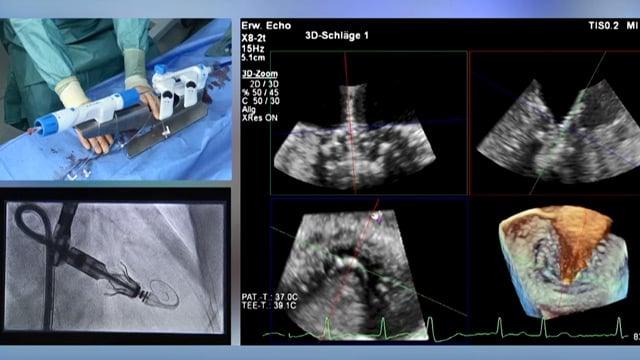

3D echocardiography for structural procedures

30 Sep 2025 – From PCR Gulf Valves 2025

This session provides an in-depth understanding of three-dimensional (3D) echocardiography in structural heart procedures. Learn how to optimize 3D echocardiographic imaging for various valve interventions, including mitral valve procedures, and gain practical skills through hands-on training to enhance procedural guidance and outcomes.